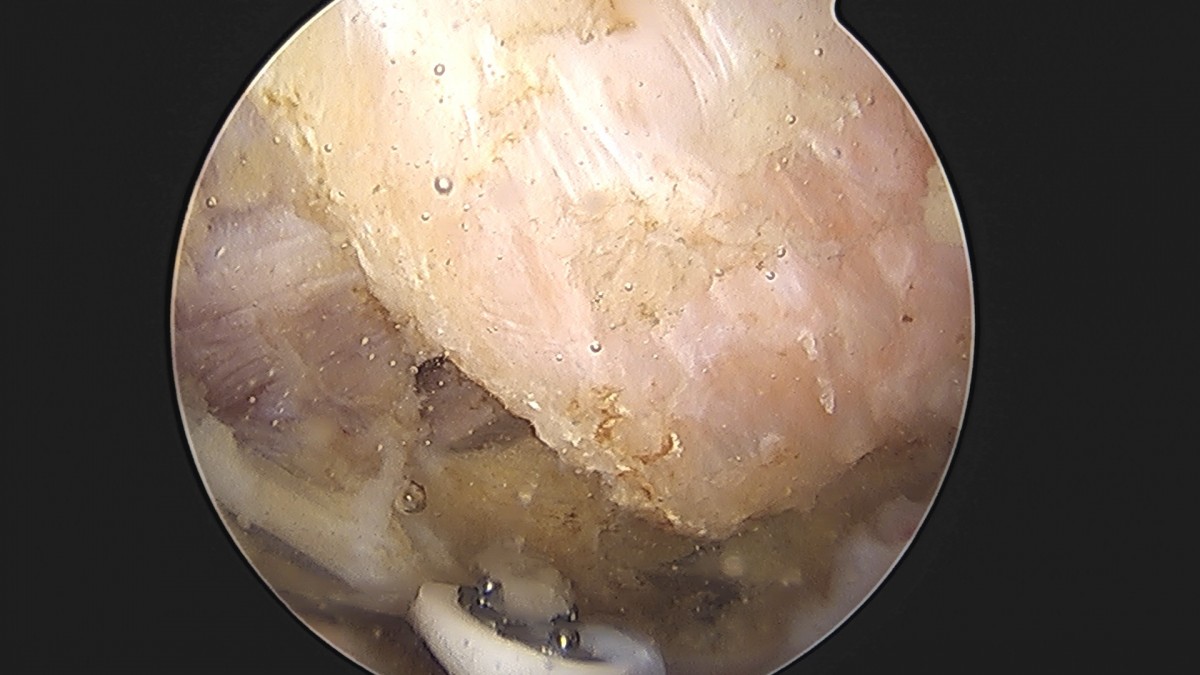

이재상원장님 어깨 견봉하 감압술 및 석회 제거술 이형O 환자

작성자 최고관리자 댓글 0건 조회 746회 작성일 25-09-16 15:40